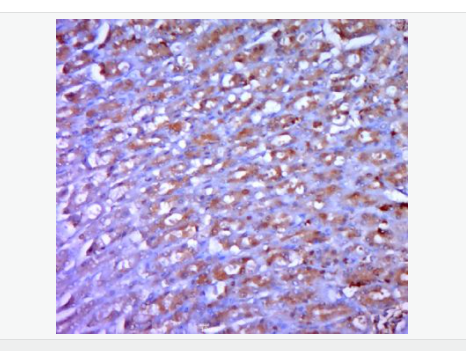

| 產(chǎn)品應用 | WB=1:500-2000 ELISA=1:5000-10000 IHC-P=1:100-500 IHC-F=1:100-500 ICC=1:100-500 IF=1:100-500 (石蠟切片需做抗原修復) not yet tested in other applications. optimal dilutions/concentrations should be determined by the end user. |

| 產(chǎn)品介紹 | The protein encoded by this gene is a member of the bone morphogenetic protein (BMP) family and the TGF-beta superfamily. This group of proteins is characterized by a polybasic proteolytic processing site which is cleaved to produce a mature protein containing seven conserved cysteine residues. The members of this family are regulators of cell growth and differentiation in both embryonic and adult tissues. This gene is thought to encode a secreted protein which negatively regulates skeletal muscle growth. Acts specifically as a negative regulator of skeletal muscle growth. [SUBUNIT] Homodimer; [TISSUE SPECIFICITY] Expressed specifically in developing and adult skeletal muscle. Weak expression in adipose tissue. Belongs to the TGF-beta family. Function: Acts specifically as a negative regulator of skeletal muscle growth. Subunit: Homodimer; disulfide-linked. Interacts with WFIKKN2, leading to inhibit its activity. Interacts with FST3. Subcellular Location: Secreted Tissue Specificity: Predominantly expressed in muscle. At hatching, expression is strongest in the skin epithelium, and is also found in the retina and brain. From day 28, expressed in skeletal muscle. In the adult, highest expression is seen in the gastrointestinal tract, brain, muscle, heart and testis. Also expressed in the adult pharynx, kidney, spleen, liver, gill, eyes, skin, swim bladder and ovary. DISEASE: Defects in MSTN are the cause of muscle hypertrophy (MSLHP) [MIM:614160]. MSLHP is a condition characterized by increased muscle bulk and strength. Affected individuals are exceptionally strong. Similarity: Belongs to the TGF-beta family. SWISS: O14793 Gene ID: 2660 Database links: Entrez Gene: 2660 Human Entrez Gene: 17700 Mouse Omim: 601788 Human SwissProt: O14793 Human SwissProt: O08689 Mouse SwissProt: O18830 Sheep Unigene: 41565 Human Unigene: 3514 Mouse Unigene: 44460 Rat Important Note: This product as supplied is intended for research use only, not for use in human, therapeutic or diagnostic applications. GDF-8又稱MSTN,是轉(zhuǎn)化生長因子超家族,也是近年來發(fā)現(xiàn)的一類重要的肌細胞生長調(diào)控因子,它通過抑制MyoD家族成員轉(zhuǎn)錄活性負向控制肌細胞的生長發(fā)育,它的表達量與肌肉重量的變化呈負相關(guān)。 |